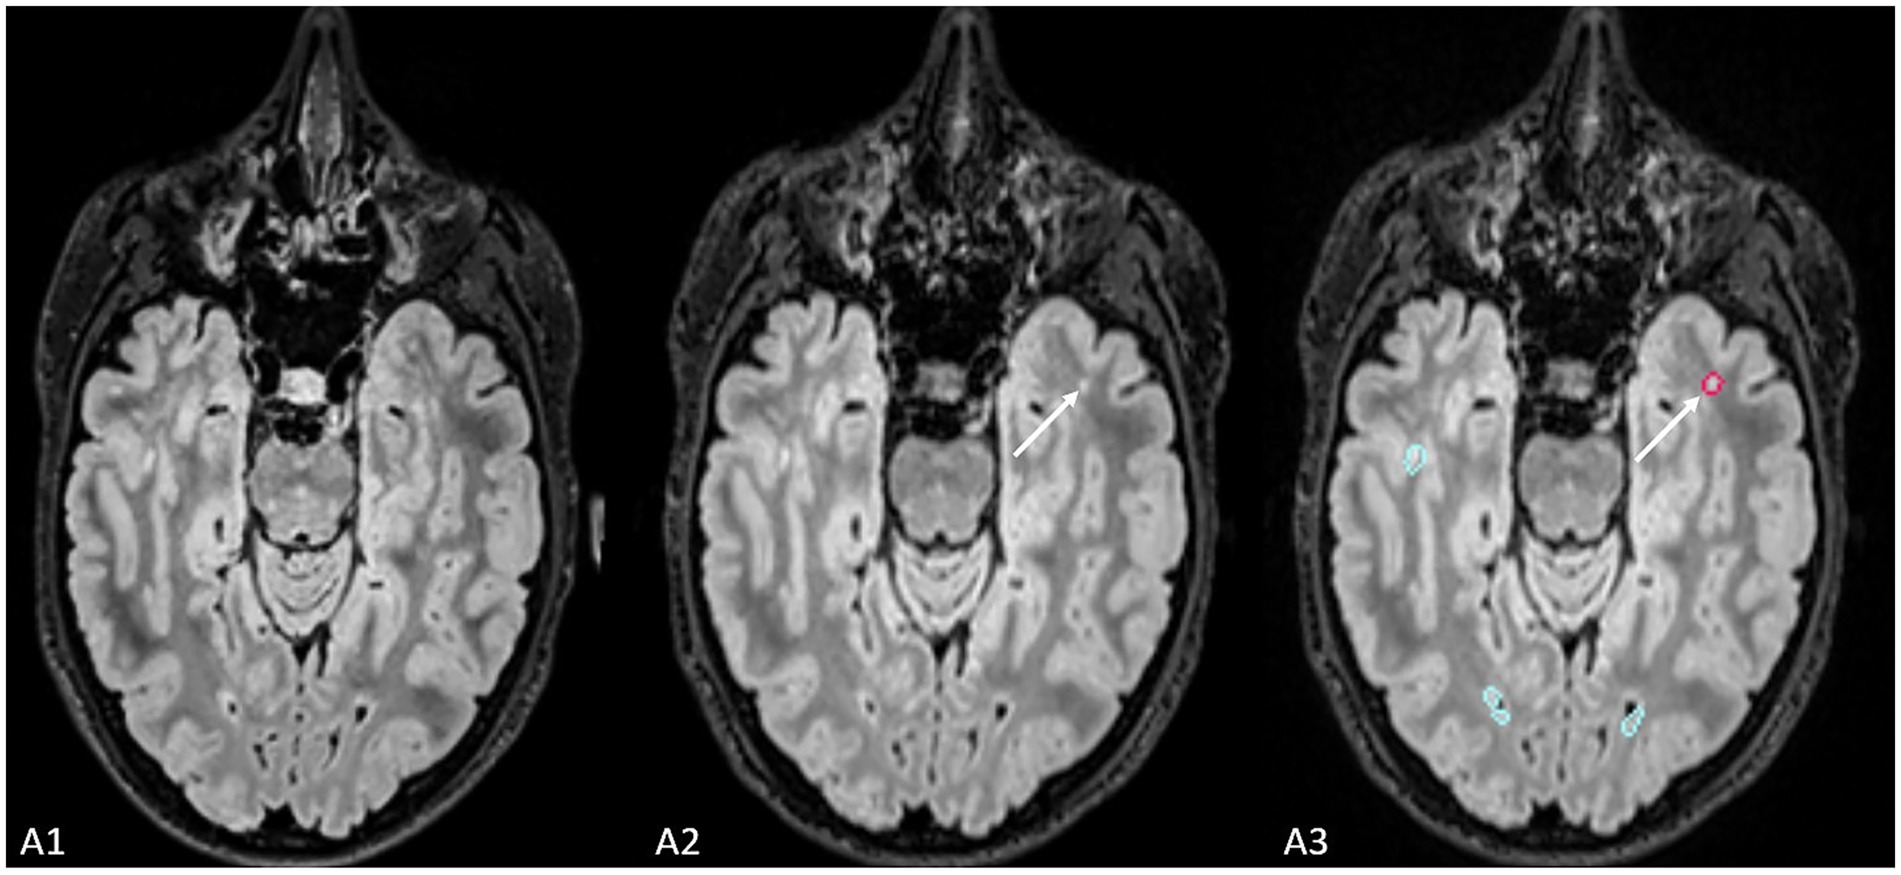

The ground truth reported 21 new lesions from 9 patients (Figure 3). With the use of Pixyl.Neuro.MS® software, reader 1 reported 19 true positive lesions from 9 patients, while reader 2 reported 20 true positive lesions from 8 patients. On the other hand, with the use of Jazz® software, reader 1 reported 19 true positive lesions in 8 patients, while reader 2 reported 17 true positive lesions in 7 patients. The standard report reported 8 new lesions in 2 patients.

Figure 3. The figure shows an example of the lesion (indicated by the white arrow) missed by radiological evaluation by Jazz® software, while it was detected by AI-assisted radiological report made using Pixyl.Neuro.MS® software.